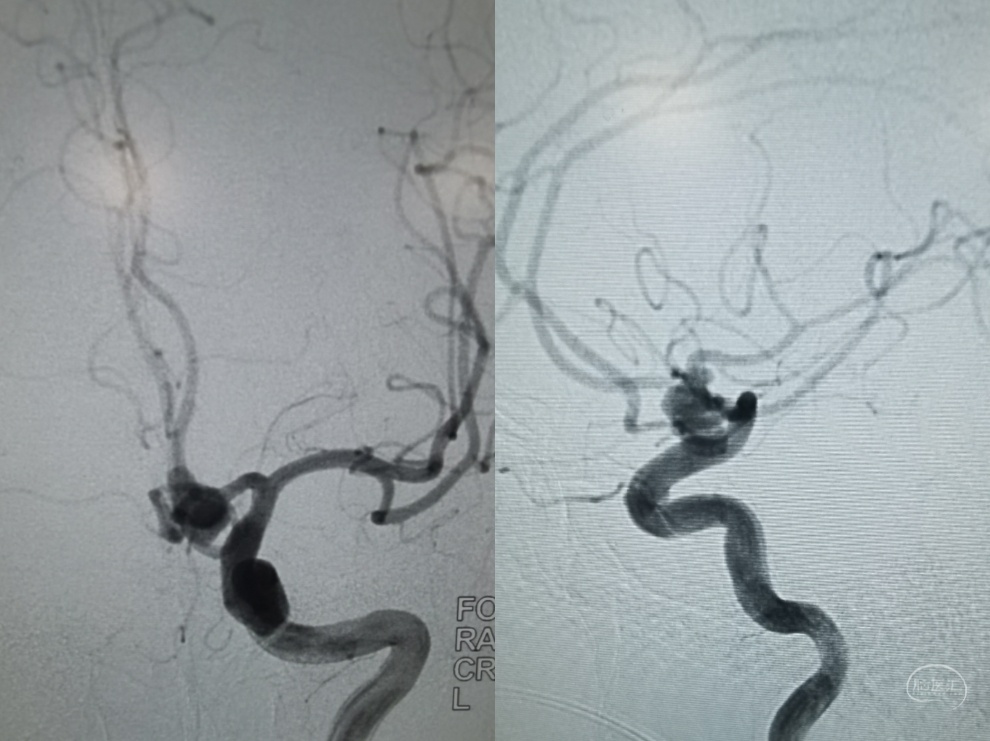

左侧颈内动脉造影正位片和侧位片,可见前交通部位大型动脉瘤,动脉瘤颈显示不清楚,左侧大脑前动脉a1段向双侧a2段供血。

左侧颈内动脉三维旋转造影可见动脉瘤位于前交通部位,累及双侧A2,形态呈长条分叶,顶端可见小子瘤。并可看到双侧a2近端血管痉挛表现

三维重建可见动脉瘤呈葫芦状,动脉瘤瘤颈累及双侧A2,没有满意的工作角度能充分展示动脉瘤瘤颈以及和双侧A2和A1的关系。

工作角度造影可以看到动脉瘤瘤体展示比较清楚,左侧A1全程清晰可见,隐约可以看到双侧A2的开口